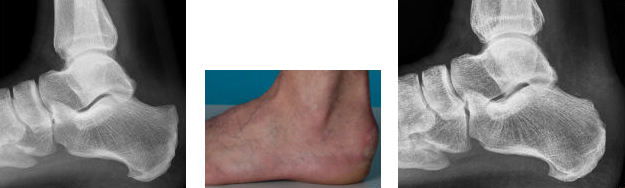

Röntgenbild und Foto vor und nach arthroskopischer Abtragung einer Haglundferse